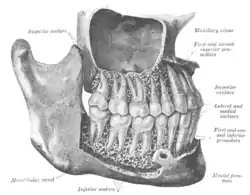

The permanent teeth, viewed from the right. The external layer of bone has been partly removed and the maxillary sinus has been opened. | |